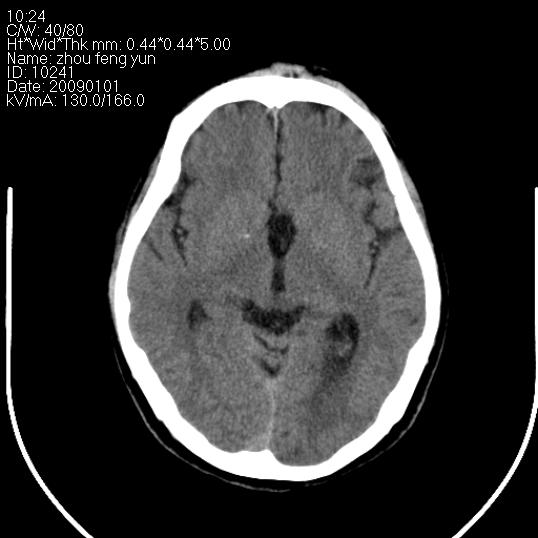

以下是引用hhcckk在2009-1-1 16:39:00的发言:[br]胼胝体嘴、膝部及部分体部发育不全,为囊状影替代,两侧侧脑室分离,脑室后角扩张[br][br]诊断:胼胝体发育不良[br][br]胼胝体发育不良(dysgenesis of the corpus callosum)是最常见的颅脑畸形,是胚胎期背部中线结构发育不良的一种形式。主要包括胼胝体缺如和部分缺如。胼胝体发育不良还可合并其他畸形,如胼胝体脂肪瘤、蛛网膜囊肿、脑膨出、chiari畸形、灰质异位症、脑回畸形等。[br][br]ct诊断要点:[br]1. ct横断扫描可见两侧侧脑室明显分离,脑室后角扩张,形成典型的蝙蝠翼状侧脑室外形。[br]2. 第三脑室扩大并向上插入两侧脑室体部之间,严重者第三脑室可上移到两侧大脑半球纵裂的顶部。在ct冠状扫描位显示更清。[br]4. 胼胝体畸形常伴有脂肪瘤,可测到其特征性脂肪密度。部分脂肪瘤的边缘可出现线样钙化[br]